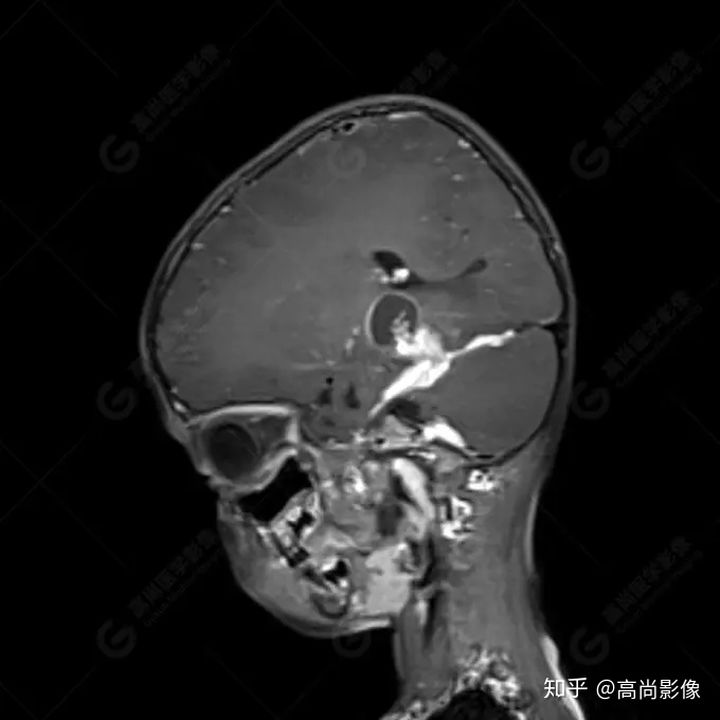

右側(cè)顳葉腫瘤切除術(shù)后(具體不詳):右側(cè)顳部骨質(zhì)不連續(xù)呈術(shù)后改變,右側(cè)顳葉術(shù)區(qū)見片狀長(zhǎng)T1長(zhǎng)T2信號(hào)影,F(xiàn)LAIR呈低信號(hào);術(shù)區(qū)后方右側(cè)顳枕葉見一巨大占位性病變影,邊界欠清,大小約6.2×5.8×4.3cm(前后×左右×上下),信號(hào)不均勻,T1WI呈等稍低信號(hào)間雜少許高信號(hào),T2WI呈高稍低混雜信號(hào),DWI示部分病灶彌散受限,相應(yīng)ADC圖減低,磁敏感序列見部分呈極低信號(hào),增強(qiáng)掃描可見明顯不均勻強(qiáng)化,鄰近硬腦膜及小腦幕增厚并明顯強(qiáng)化;另延髓右前方及右側(cè)橋小腦角區(qū)見一不規(guī)則形異常信號(hào)影,大小約3.2×1.3×3.7cm(左右×前后×上下),呈長(zhǎng)T1稍長(zhǎng)T2信號(hào),F(xiàn)LAIR呈等信號(hào),DWI未見受限,增強(qiáng)后明顯均勻強(qiáng)化,鄰近腦膜明顯強(qiáng)化。鄰近腦實(shí)質(zhì)及右側(cè)顳角明顯受壓;左側(cè)大腦半球未見局灶性信號(hào)異常,中線結(jié)構(gòu)稍左移。

右側(cè)顳葉腫瘤切除術(shù)后:現(xiàn)術(shù)區(qū)后方右側(cè)顳枕葉及延髓右前方占位,右側(cè)顳枕部硬腦膜及小腦幕明顯強(qiáng)化,結(jié)合既往影像資料,考慮為胚胎源性惡性腫瘤,如非典型畸胎樣/橫紋肌樣瘤(AT/RT)或原始神經(jīng)外胚層腫瘤(PNET)。